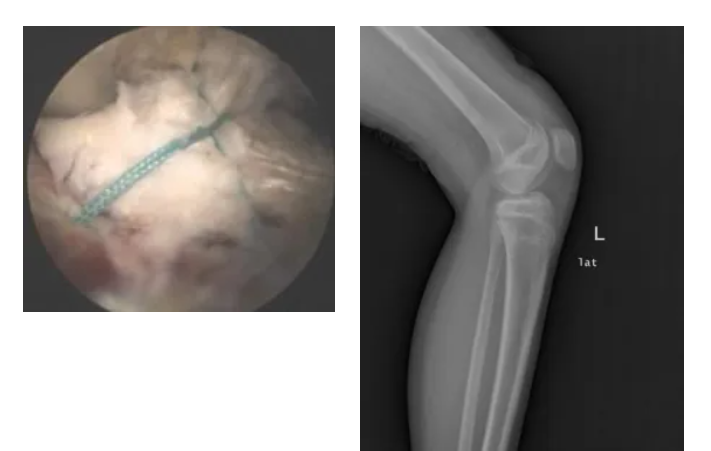

02.交叉韌帶止點(diǎn)骨折(脛骨髁間棘骨折)

關(guān)節(jié)鏡下微創(chuàng)韌帶復(fù)位固定骨折

03.半月板損傷

關(guān)節(jié)鏡下微創(chuàng)行半月板成形、部分切除、盤(pán)狀半月板切除、半月板撕裂縫合等